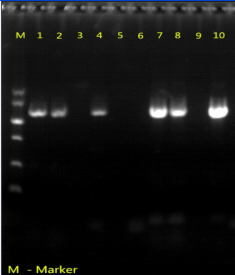

樣品經 PCR 檢測,瓊脂糖凝膠電泳可見一條約1200bp 的目的條帶,而陰性對照無任何條帶,說明病料中含有Ⅰ群IV型禽腺病毒,樣品檢測結果安卡拉病為陽性。

病料PCR檢測結果

M為Marker ??1-4泳道為尿囊液,7-10為病料,5-6空白對照